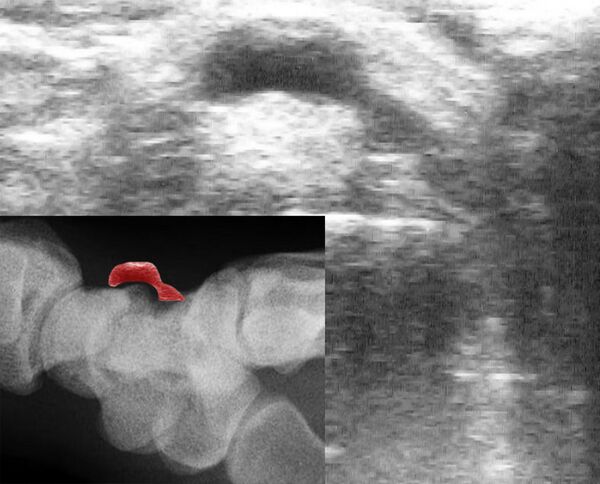

Синовиальные кисты легко диагностируются, так как они хорошо видны невооружённым глазом и легко пальпируются.[16]

Для повышения достоверности диагностики при клинически подозрительных поражениях или для выявления небольших «скрытых» кист как причины боли в тыльной части запястья при сильном разгибании может назначаться ультразвуковое исследование[16]

Диагноз ставится на основании клинической картины. При нетипичной локализации проводится рентгенологическое или ультразвуковое исследования, для исключения злокачественности может проводиться пункция с последующей гистологией и цитологией.